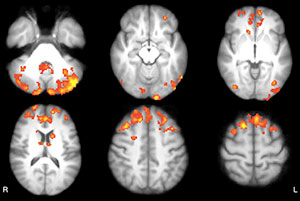

Figure 3. Axial functional connectivity (FC) maps show changes in thalamic FC after 8 weeks in both groups of patients with MS. Areas of increased FC are represented in red, areas of reduced FC in blue. A, Intervention group shows increased FC in occipital, medial, and lateral parietal and posterior cingulate cortices, bilaterally; decreased FC in vermis and left dorsal-lateral prefrontal cortex. B, Wait-list group shows increased FC in frontal, occipital, and medial parietal cortices, bilaterally; cerebellum; and right temporal lobe.